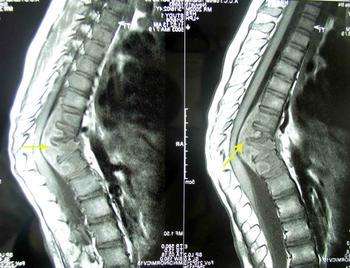

骨结核一定需要抗结核治疗,需不需要手术治疗看情况。脊椎结核患者,如果脊椎破坏严重,如造成骨缺损严重,严重畸形等。需要考虑植骨、固定等治疗方法。

当然有。有些脊椎结结核患者在手术后几年会出现行动不便的现象,或者在手术后就会出现这种情况,因为脊椎比较复杂,治疗难度比较大。但是如果患者确实需要固定或者植骨治疗,最好到有口碑的医院进行治疗。